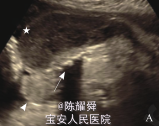

查体:一般情况可,心肺体查无明显异常,产科检查:宫高 32cm,腹围 98cm,胎心 140次/分。 孕35+2周B超:宫腔内探及一结构正常胎儿(泵血儿)及一不规则球形含骨性包块(无心畸胎儿) 。1个胎盘,两胎儿间见纤细光带分隔。无心畸胎儿固定于宫腔右下方,羊膜光带紧贴胎儿周边,大小为 9.3cm×7.0cm×5.1cm,无头、无心、无上肢,全身皮肤明显水肿,厚约 2.4cm, 内可见不规则骨性结构, 光团远端见一小肢体样结构(图1) ,腹部可见 1.5 cm 连续性中断,中断处可见 3.0 cm ×2.8 cm肿块向外膨出,内可见肠管回声。体内及脐血管内可见血流信号,脐动脉反向灌注朝向胎儿体内,脐动脉搏动指数1.06,阻力指数 0.67,收缩期 / 舒张期比值 3.0(图 2) 。